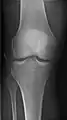

- Knee - AP and Lateral. Intra Condular projections on request

Right knee, anteroposterior

Right knee, lateral